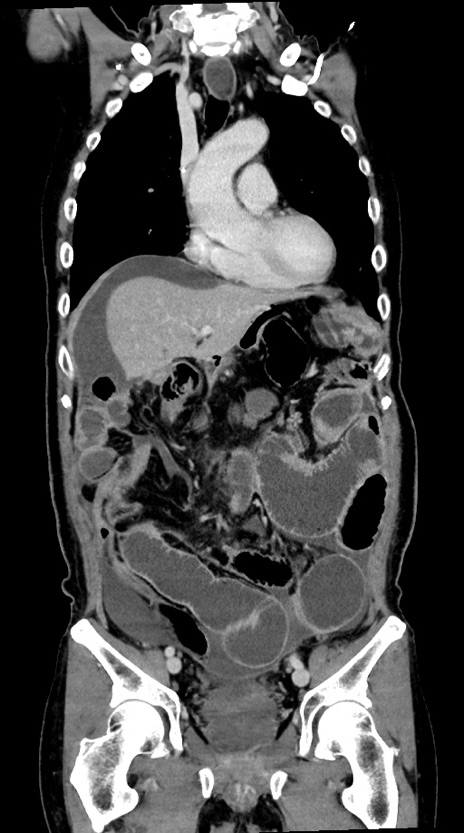

症例28(冠状断像)

【症例】60歳代男性

【主訴】嘔吐

【現病歴】胃癌にて胃全摘後。食思不振が悪化し、夜中に嘔吐することがある。

【既往歴】胃癌、胃全摘、脾摘、胆摘後

【データ】WBC 5900、CRP 10.56